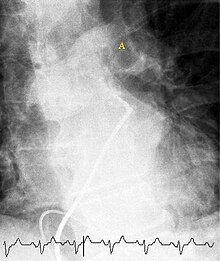

Selective pulmonary angiogram revealing clot (labeled A) causing a central obstruction in the left main pulmonary artery. ECG tracing shown at bottom.

Historically, the gold standard for diagnosis was pulmonary angiography by fluoroscopy, but this has fallen into disuse with the increased availability of non-invasive techniques that offer similar diagnostic accuracy.[60]